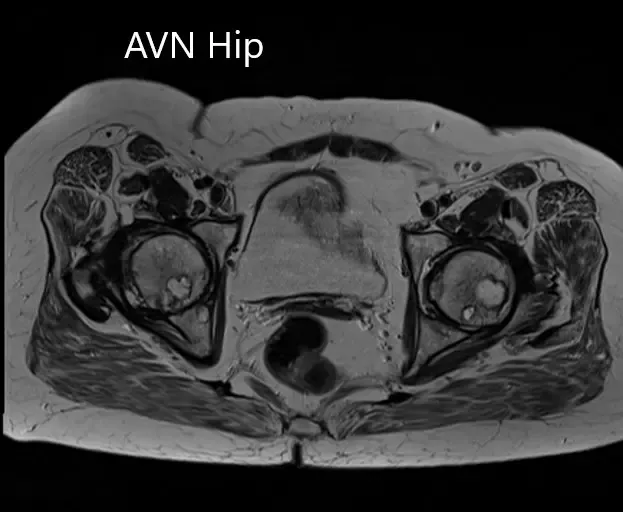

MRI was obtained which showed:

Right Hip Joint: There is a loss of sphericity of right femoral head, involving more than 2/3 of the circumference. In the superior part of the right femoral head, a focal lesion is visualized which is bounded by a serpiginous T1 hypointense margin. The lesion is hypointense on both T1 & T2WI relative to the marrow (Mitchell class – D).

No subchondral fracture is detected. A minimal amount of fluid is seen in the joint cavity. The femoral neck and acetabulum display normal signal intensity. Muscles in view display normal signal intensity.

Left hip joint: Displays similar although less severe changes. The sphericity of the left femoral head is maintained. There is more than 2/3 circumferential involvement of the left femoral head. No subchondral fracture is seen. No joint effusion is seen.

Axial sections of T1WI and T2WI of the pelvis MRI.